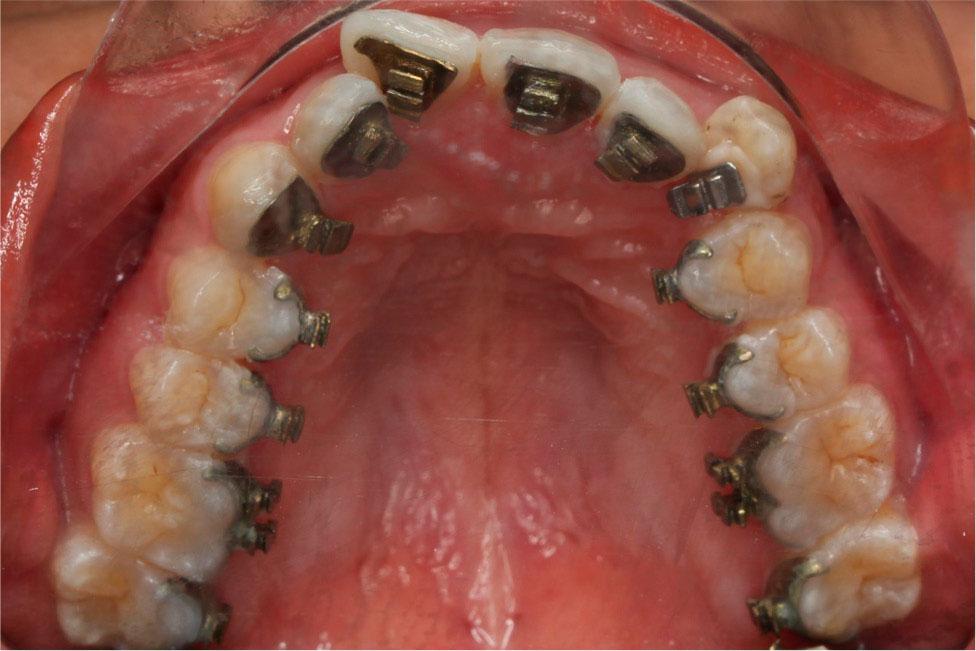

Treatment commenced by bonding all teeth with 0.018” × 0.025” double-slotted customised lingual brackets except the mandibular right central incisor due to inadequate space. A dual-cured resin cement (RelyX U200, 3M Unitek, Monrovia, CA, USA) or a low-viscosity orthodontic adhesive (Enlight, Ormco, Glendora, CA, USA) combined with a universal primer (Single Bond Universal, 3M Unitek, Monrovia, CA, USA) may be used. The initial alignment and levelling were achieved using 0.012”, 0.014”, and 0.016” nickel-titanium round arch wires combined with open coil springs to open space for the mandibular right central incisor and left second premolar. Because of the flexibility of nickel-titanium arch wires, they were difficult to shape and so stock arch wires (Lingual straight wire, Ormco, Glendora, Calif) were selected from three standard arch forms at this initial period.12,13 The arch wire customisation is of minimal importance at this early stage because the nickel-titanium arch wires would not immediately express their arch form due to their flexibility. After gaining enough space, the mandibular right central incisor was bonded directly guided by the customised bracket base. The arch wire sequence was restarted from a 0.012” nickel-titanium round arch wire and progressed through stiffer arch wires.

After 5 months of levelling and alignment, the overjet increased and a Class II molar and canine relationship developed on the left side (Figure 7). Using a diamond disc (SuperFlex, Edenta, Kaltbrunn, Switzerland), interproximal reduction was performed in both arches from the left to the right first molars which reduced the proximal surface of each tooth by approximately 0.3 mm. Two miniscrews (diameter, 1.6 mm; length 8 mm; Medico, Gyeonggi-do, Korea) were placed in the palatal alveolar bone between the maxillary first and second molars. Entire upper arch distalisation forces of approximately 200 g on each side were applied by power chain from the miniscrews to four anterior lingual brackets. Power chains were also applied to the lower arch to close interproximal reduction spaces. The patient was also instructed to wear Class II elastics on the left side and anterior cross elastics (3/16-inch, 3.5 oz) for lower midline correction.

After 5 months of distalisation, a normal overjet and co-incident midlines were obtained. Two labial ceramic brackets were bonded to the maxillary first and second premolars and first-order bends were placed in 0.016” × 0.022” stainless steel customised arch wires to improve tooth alignment (Figure 8). Additionally, labial composite buttons were bonded to apply vertical elastics for occlusal settling. The finishing stage, which took 2 months, resulted in a total treatment time of 12 months. After appliance removal, fixed retainers were bonded to both arches for long-term stability.